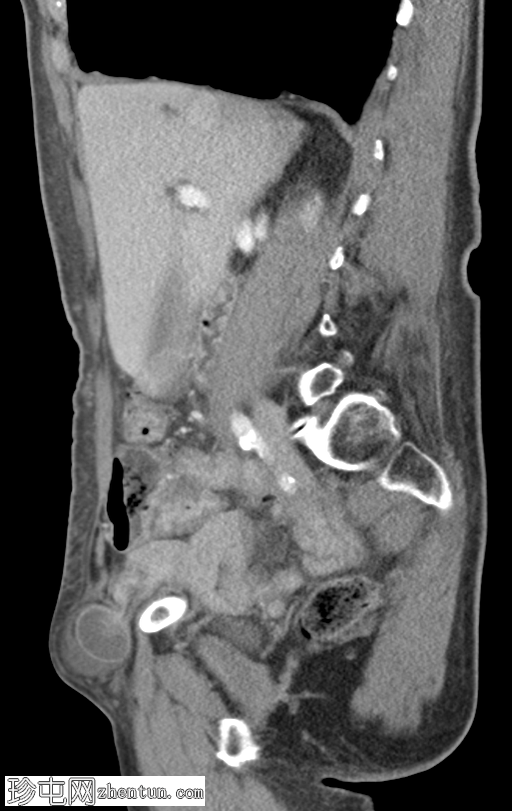

矢状位增强扫描(门静脉期)

可见右侧股疝嵌顿,右侧股静脉受压,输出小肠袢塌陷,输入小肠袢扩张。可见中等量周围游离液体。无缺血征象。右侧努克氏管向内侧移位。疝颈位于腹壁下动脉起始部和腹股沟韧带下方。

肝脏可见多个小囊肿。左侧肾上腺肿大,内含低强化结节。

股总静脉受压、疝颈狭窄、女性、努克氏管向内侧移位、疝颈起源于腹壁下动脉起始部和腹股沟韧带下方等表现,更倾向于股疝而非腹股沟疝。